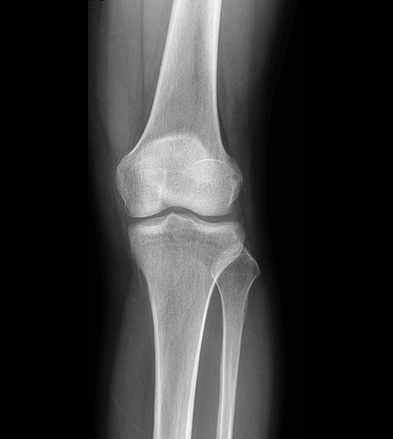

平板探测器

超高像素

高清点片